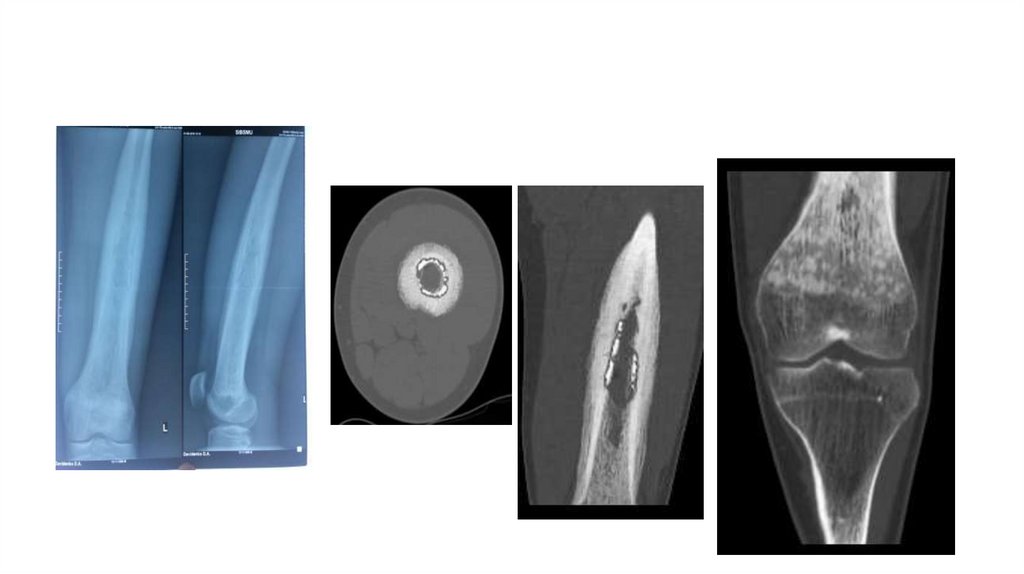

«Воспалительные

заболевания опорнодвигательного аппарата»